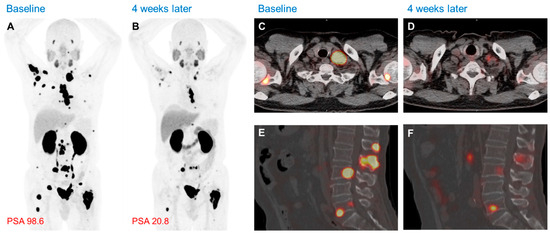

- Hofman, M.S.; Emmett, L.; Sandhu, S.; Iravani, A.; Joshua, A.M.; Goh, J.C.; Pattison, D.A.; Tan, T.H.; Kirkwood, I.D.; Ng, S.; et al. Lu-177 PSMA-617 versus cabazitaxel in patients with metastatic castration-resistant prostate cancer (TheraP): A randomised, open-label, phase 2 trial. Lancet 2021, 397, 797–804. [Google Scholar] [CrossRef]

- Sartor, O.; de Bono, J.; Chi, K.N.; Fizazi, K.; Herrmann, K.; Rahbar, K.; Tagawa, S.T.; Nordquist, L.T.; Vaishampayan, N.; El-Haddad, G.; et al. Lutetium-177 PSMA-617 for Metastatic Castration-Resistant Prostate Cancer. N. Engl. J. Med. 2021, 385, 1091–1103. [Google Scholar] [CrossRef]